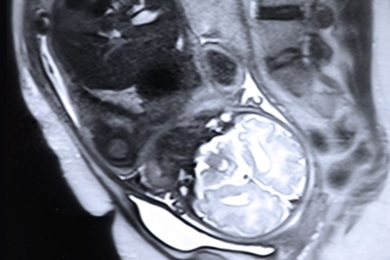

Using artificial intelligence to improve early breast cancer detection

Model developed at MIT’s Computer Science and Artificial Intelligence Laboratory could reduce false positives and unnecessary surgeries.